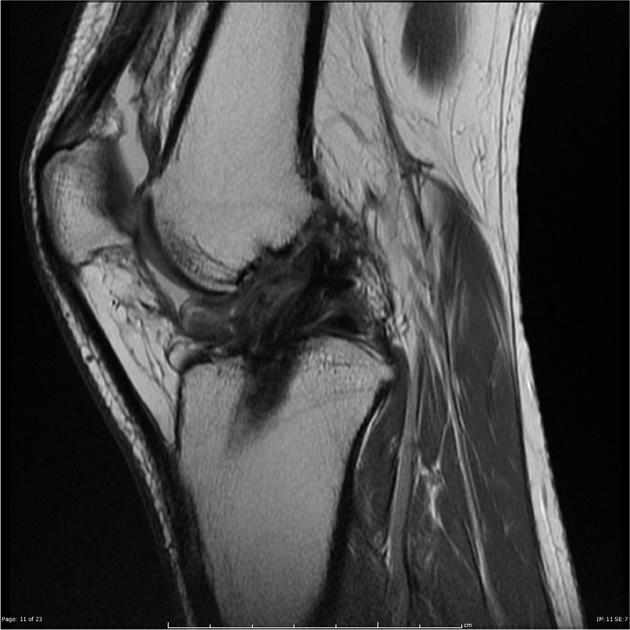

Badania obrazowe:

• MRI: uwidacznia blizny, zrosty wewnątrzstawowe i zmiany w torebce/mięśniach.